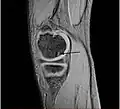

Magnetic resonance imaging (MRI) is useful for staging OCD lesions, evaluating the integrity of the joint surface, and distinguishing normal variants of bone formation from OCD by showing bone and cartilage edema in the area of the irregularity. MRI provides information regarding features of the articular cartilage and bone under the cartilage, including edema, fractures, fluid interfaces, articular surface integrity, and fragment displacement.[37][38] A low T1 and high T2 signal at the fragment interface is seen in active lesions. This indicates an unstable lesion or recent microfractures.[30] While MRI and arthroscopy have a close correlation, X-ray films tend to be less inductive of similar MRI results.[38]